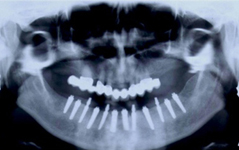

Jsou zavedeny do kosti horní nebo dolní čelisti a umožňují náhradu jednoho, několika či všech zubů pomocí korunek, můstků, které jsou na ně připevněny nebo tvoří podporu pro zubní protézy.

• Zavedení implantátu do kosti čelisti

• Zahojení do kosti – 3-4měsíce(v některých případech i déle – doplňování kosti)

Bezzubá čelist je hlavní indikací pro ošetření pomocí implantátů. Zejména celkové zubní náhrady v dolní čelisti mají velice nízkou stabilitu a držení díky velkému úbytku kosti.

S pomocí zubních implantátů můžeme díky různým kotevním systémům (třmeny, kulové hlavy, Locatory) zajistit stabilitu a držení protézy nebo při použití většího počtu implantátů zhotovit pevné náhrady – můstky nalepené nebo našroubované na pevno na implantáty.